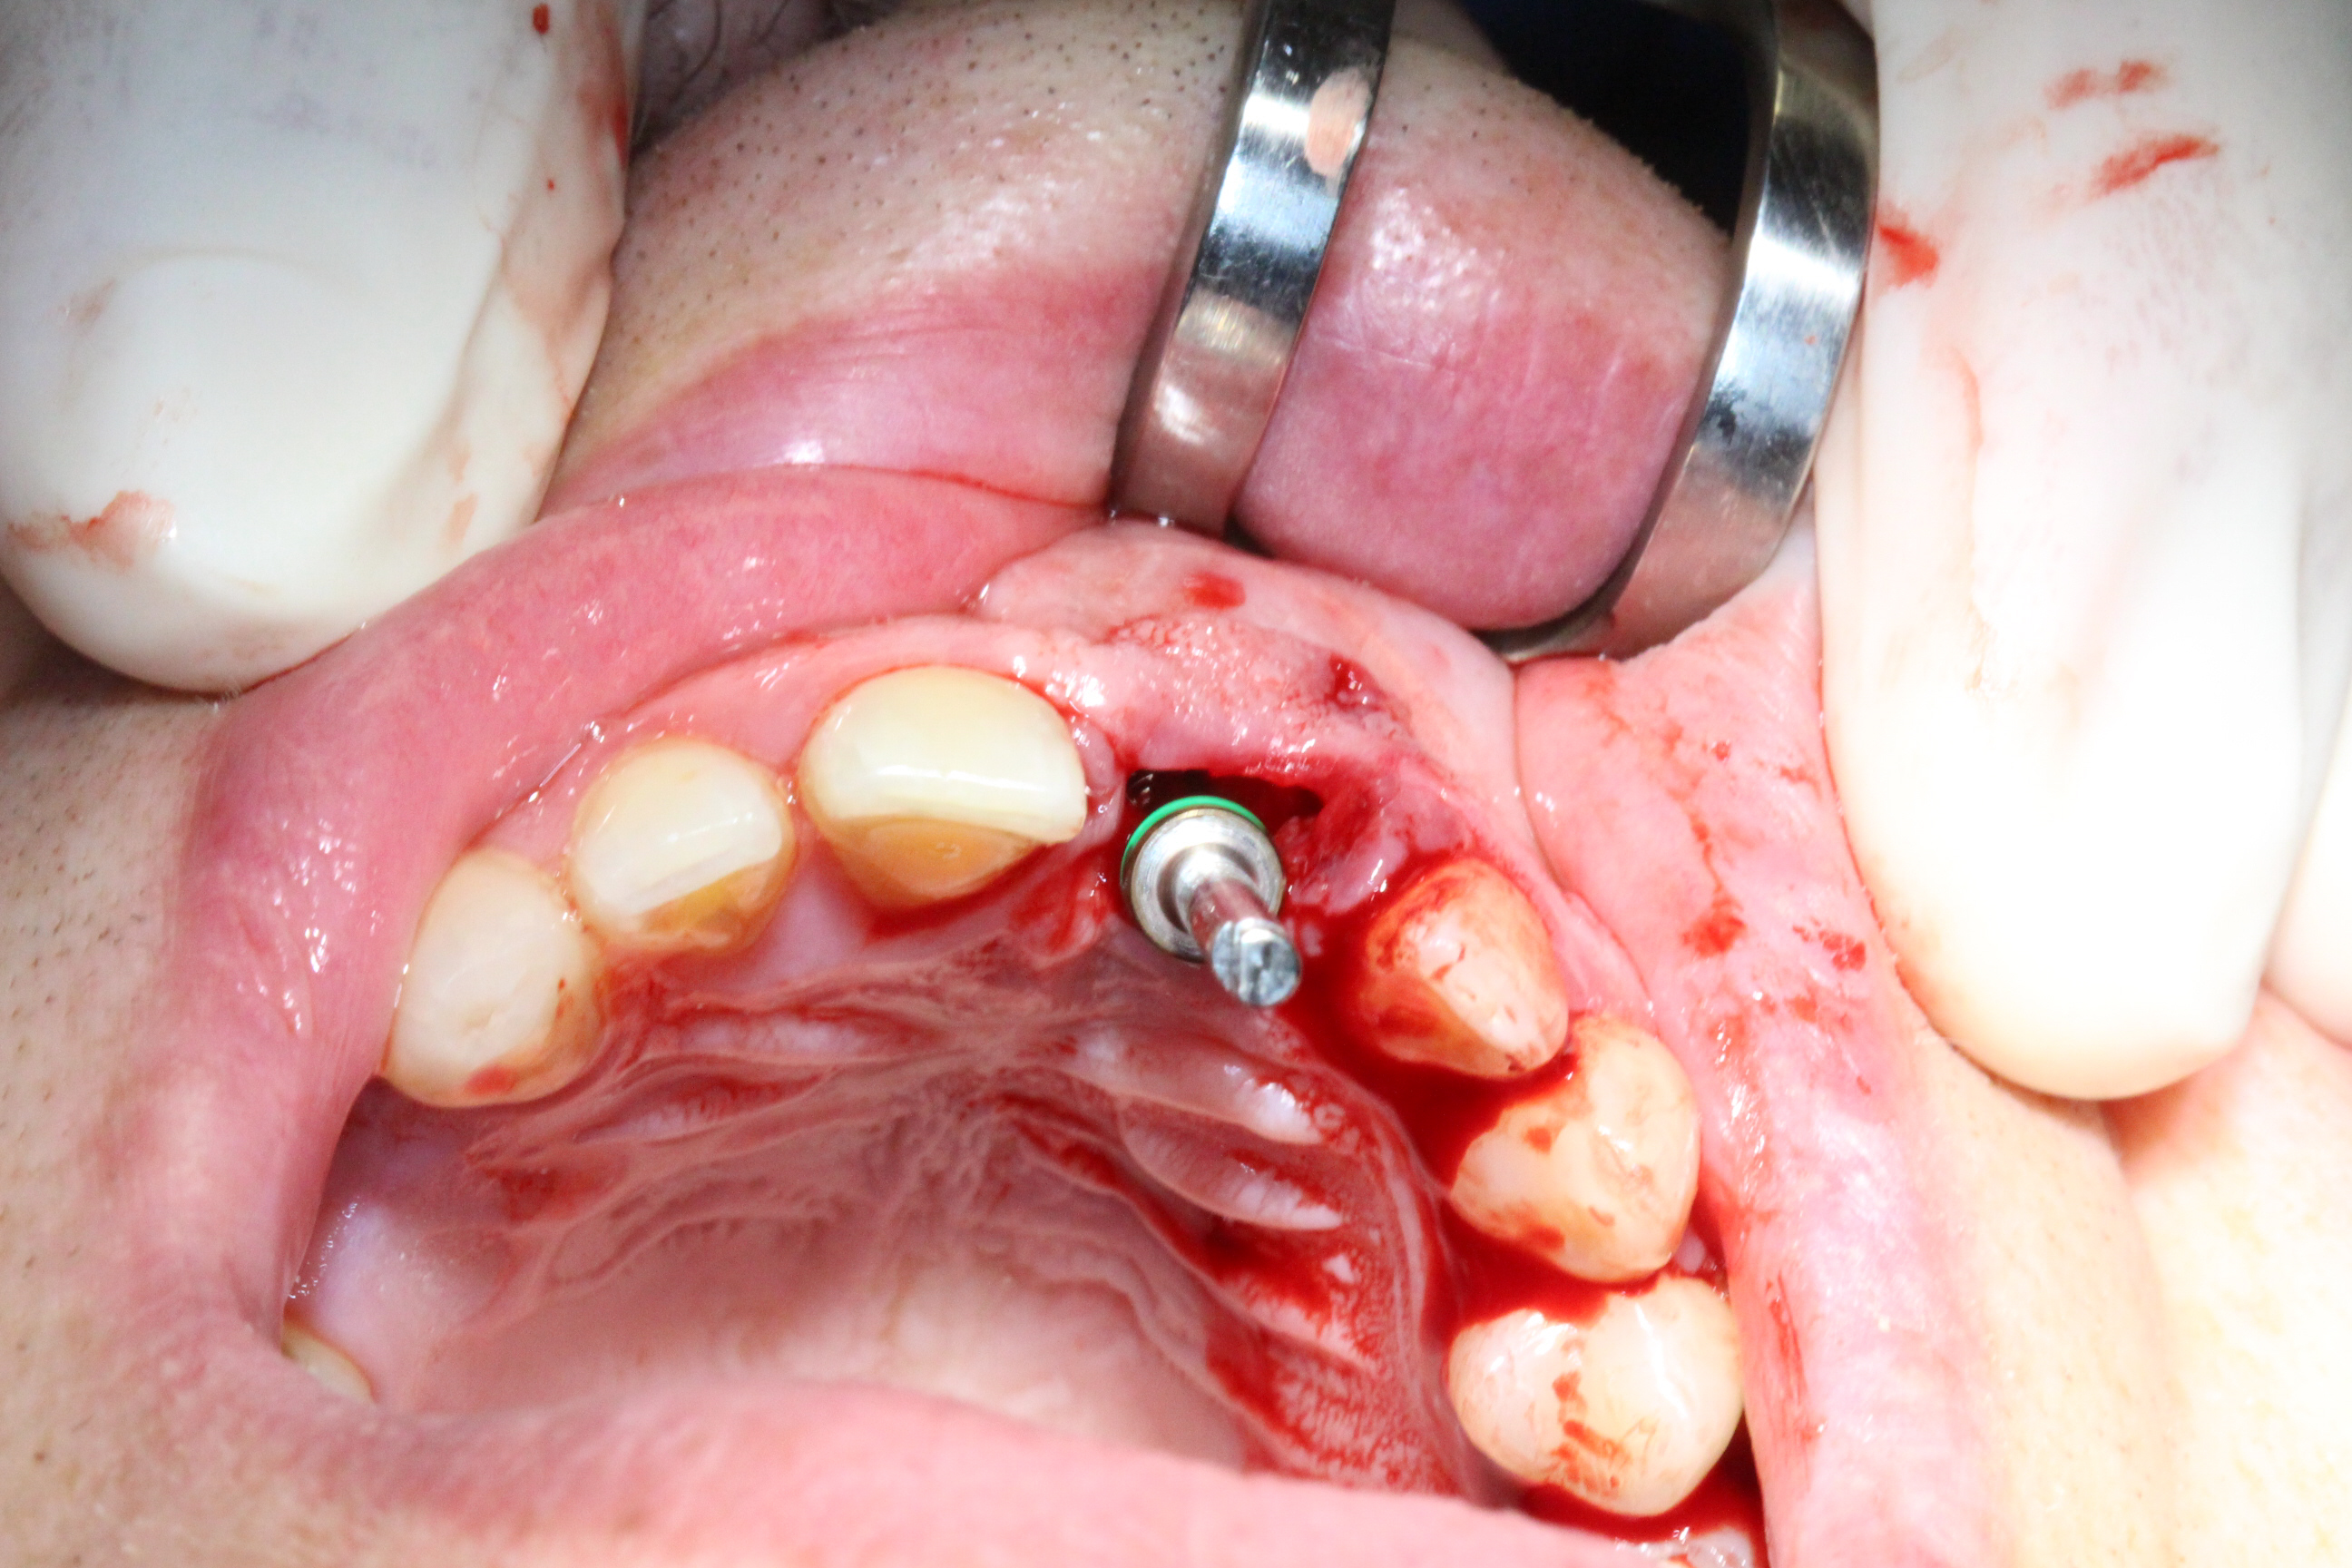

Immediate Loading

The prosthetic phase was performed by Dr. Simon Budak.

A Multi-Unit Abutment (MUA 1.6) was connected to the implant. Using a titanium sleeve, a temporary crown was fabricated chairside, and the implant was immediately loaded. Benefits of this approach included preservation of the extraction socket, maintenance of the interdental papilla, immediate restoration of aesthetics, and high patient satisfaction.

The patient left the clinic with a temporary crown on the day of surgery and was advised to follow a soft-food diet for the first month.